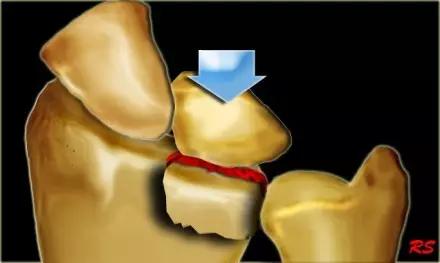

5. Kocher-Lorenz 骨折

单纯肱骨小头骨折。

Kocher-Lorenz 骨折(来源:The often-missed Kocher-Lorenz elbow fracture. Revue de Chirurgie Orthopédique et Traumatologique, Volume 95, Issue 7, November 2009, Pages 658-661)

6. Hahn-steinthal 骨折

全肱骨小头骨折,为一种少见的关节内骨折,多见于成年人。常由于跌倒时手过度伸直或在屈肘时因桡骨小头撞击肱骨小头,并同时有外翻力存在时发病,亦可伴有滑车骨折与内侧副韧带的撕裂。X 线表现为全肱骨头骨折,向上移位。

Hahn-steinthal 骨折 X 片(来源:Hahn-Steinthal fracture: a case report.BioMed central Cases Journal20081:239)

Hahn-steinthal 骨折 CT 片(来源:Hahn-Steinthal fracture: a case report.BioMed central Cases Journal20081:239)